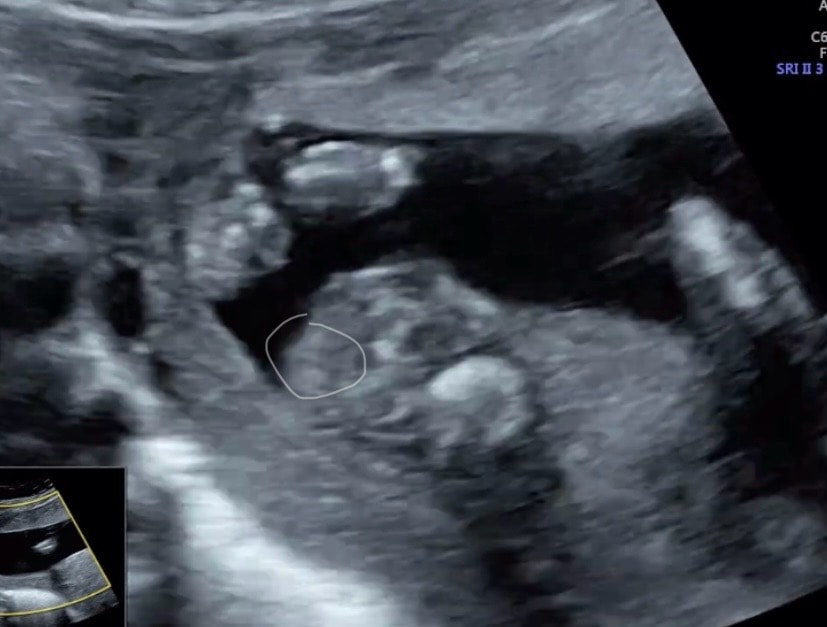

❆Elena❆, да я уверена была, сын. Уже и кое что ему купила… теперь в мае спрошу. Изображение Вот наверху дочка моя, внизу сейчас. Изображение А еще вот. Девочки мне сказали губы и клитор торчит

11.04.2025

Алина, ну как бы да, это не похож на писюн! Дай бог вам здоровую девочку!!